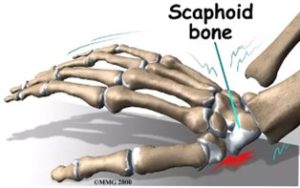

شکستگی استخوان اسکافوئید ( Scaphoid ) رایج ترین شکستگی استخوان های مچ است و تشخیص و درمان شکستگی های مچ اغلب دشوار است. این شکستگی در افراد بزرگسال جوان در اثر افتادن با دستان باز ( Falling On Outstretched Hand ) اتفاق میفتد( شکل ۱ ) . این شکستگی ممکن است که نادیده گرفته شود و فرد آن را بعنوان کشیدگی تاندون در نظر بگیرد یا ممکن است در اوایل در عکس رادیولوژی ساده قابل مشاهده نباشد . این شکستگی ممکن است دچار جوش نخوردگی شود یا اینکه بد جوش بخورد که که حرکات دست را دستخوش تغییر میکند و میتواند باعث درد و کاهش دامنه حرکتی و قدرت و آرتروز زودهنگام مچ دست شود . بهبودی، اغلب آهسته است و در بعضی موارد ممکن است جوش نخورد. برای احتیاط، در مراحل اولیه ، دست در گچ قرار میگیرد و دوباره بعد از چند هفته عکس رادیولوژی ساده میگیرند اگر شکستگی در عرض یک هفته بعد از بی حرکتی تشخیص داده شود جوش نخوردن میتواند پیشگیری شود. اگر شکستگی در کمر استخوان رخ دهد خونرسانی بخش پروکسیمال مختل شده و ممکن است باعث مرگ بافت استخوانی درنتیجه فقدان خونرسانی شود. ( شکل ۲ ) . عوارض بلند مدت میتواند باعث بروز آرتروز این ناحیه شود.

(شکل ۱) : افتادن با دستان باز ( Falling On Outstretched Hand )